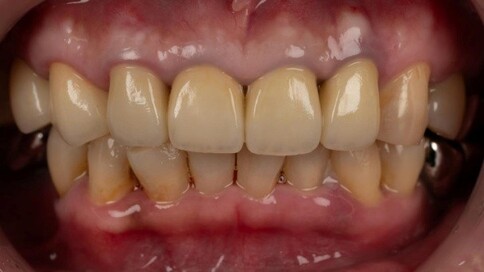

✨ 三、 四至六顆:微笑曲線重塑

Case 7:外突內收打造理想笑線,提亮色階。

Case 8:拆除舊連排假牙,換成獨立顆數全瓷冠。